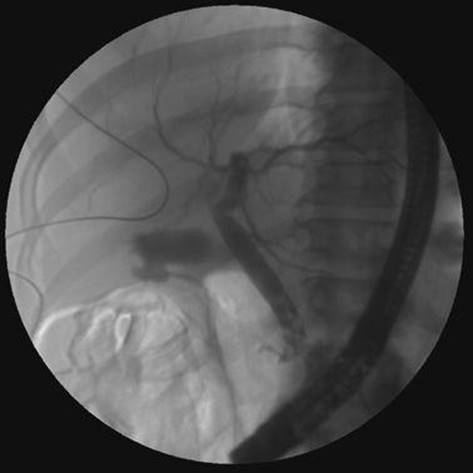

A 56-year-old man presents for evaluation of jaundice. He had been well until 3 weeks ago when he noticed the onset of mild mid-epigastric pain, which resolved spontaneously. His past medical and surgical histories were unremarkable. He reported an 8-pound weight loss, which he blamed on a lack of appetite. Examination was notable only for jaundice and icteric conjunctivae. Laboratory tests revealed a total bilirubin of 8.6 mg/dL and an alkaline phosphatase of 565 IU/L. Aminotransferases were only slightly elevated. Amylase and lipase were normal. An abdominal ultrasound demonstrated a dilated extrahepatic bile duct. What is the next most appropriate test?

ERCP.

In the previous case, an ERCP was done with the finding below. What would you do next?

Figure 39-2

Endoscopic sphincterotomy with stone extraction.